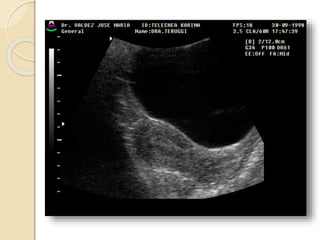

FIBROMA O LEIOMIOMA UTERINO

Patología común del útero que ocurre aproximadamente

en el 40% de las mujeres mayores de 35 años.

Los fibromas habitualmente son múltiples y más

comúnmente asintomáticos.

Se clasifican en:

• Submucosos: son los menos frecuentes pero es mas

probable que produzcan síntomas.

• Intramurales: Es el tipo mas común.

• Subserosos: Con frecuencia son pediculados y

pueden simular masas anexiales.